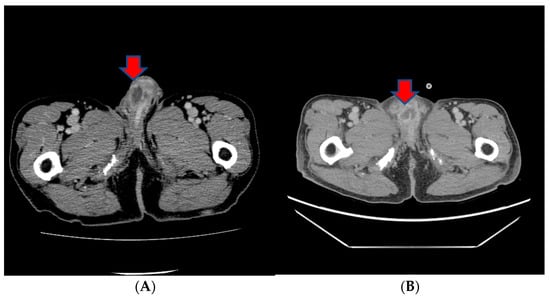

However, in a subsequent CT scan performed approximately 4 months later, an increased size of the mass in the penis was observed, and persistent penile pain led to the consideration of radiation therapy (Figure 4). After radiation therapy, a follow-up CT scan showed a decreased tumor size (5.1 cm to 3.4 cm) (Figure 4).

Figure 4.

(A) A subsequent CT scan performed approximately 4 months later showing an increased size of the mass in the penis. (B) After radiation therapy, a follow-up CT scan showed the decreased size of the tumor.